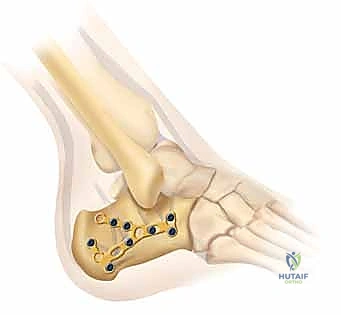

يتم وضع شريحة تيتانيوم (Titanium Plate) مصممة خصيصاً لتطابق الشكل التشريحي لعظم الكعب. يتم تثبيت هذه الشريحة بمسامير قوية لتوفير ثبات ميكانيكي صلب يسمح بالالتئام السليم ويمنع انهيار العظم مرة أخرى. في بعض الحالات التي يوجد فيها فراغ عظمي كبير، قد يستخدم الدكتور هطيف طعوماً عظمية (Bone Grafts) لملء الفراغ.

صور إضافية من داخل غرفة العمليات توضح دقة الإجراء

توضح الصور التالية مدى تعقيد الجراحة والدقة التي يتطلبها تثبيت عظم الكعب، والتي يعكسها التميز الجراحي للأستاذ الدكتور محمد هطيف: